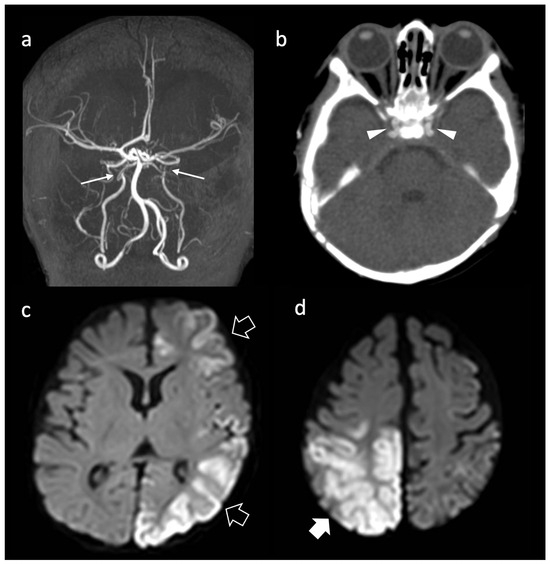

Background: Heterozygosity for pathogenic variants in the ABCC6 gene has been associated with an increased incidence of cerebrovascular diseases. This study aims to characterize the prevalence and clinical and neuroradiological phenotypes associated with monoallelic and biallelic ABCC6 variants in pediatric and adult patients presenting with arterial ischemic stroke or cerebral small vessel disease (CSVD). Methods: We conducted a retrospective observational study on 143 consecutive patients (48 pediatric, 24 juvenile, 71 adult) diagnosed with ischemic stroke or CSVD of unknown etiology. Clinical and neuroradiological data were collected and analyzed in relation to the identified genetic variants through next-generation sequencing. Results: Among the patients, 16 (11.2%) tested positive for causative variants in the ABCC6 gene, with 11 subjects carrying monoallelic variants and 5 carrying biallelic variants. Patients with biallelic variants exhibited severe and complex vasculopathy, with a high incidence of early ischemic events. In contrast, monoallelic carriers predominantly presented with microvascular disease manifestations, including lacunar strokes and signs of CSVD. Conclusions: The results suggest a significant age-dependent phenotypic divergence in patients with ABCC6 variants, highlighting the impact of heterozygosity on cerebrovascular health. Identifying these variants may enhance risk stratification and inform management strategies in patients with traditional vascular risk factors. Full article